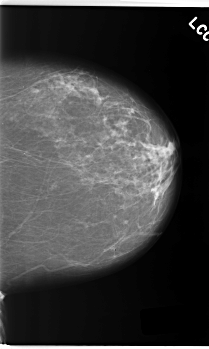

C_0214_1.LEFT_CC

LEFT_CC LINES 5928 PIXELS_PER_LINE 3544 BITS_PER_PIXEL 12 RESOLUTION 50 NON_OVERLAY